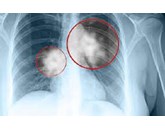

Chẩn đoán ung thư phổi 05/08/2023 Ung thư phổi thường không biểu hiện triệu chứng cho đến khi nó ở giai đoạn cuối, điều đó có nghĩa là kết quả điều...

Triệu chứng ung thư phổi 05/08/2023 Ung thư phổi thường không có bất kỳ triệu chứng nào trong giai đoạn đầu của bệnh, có nghĩa là rất khó phát hiện và...